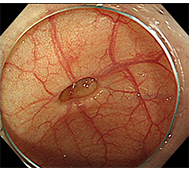

食道がん

- 内視鏡治療 :病変がリンパ節転移の無い早期食道がんに対し、内視鏡治療が行われます。